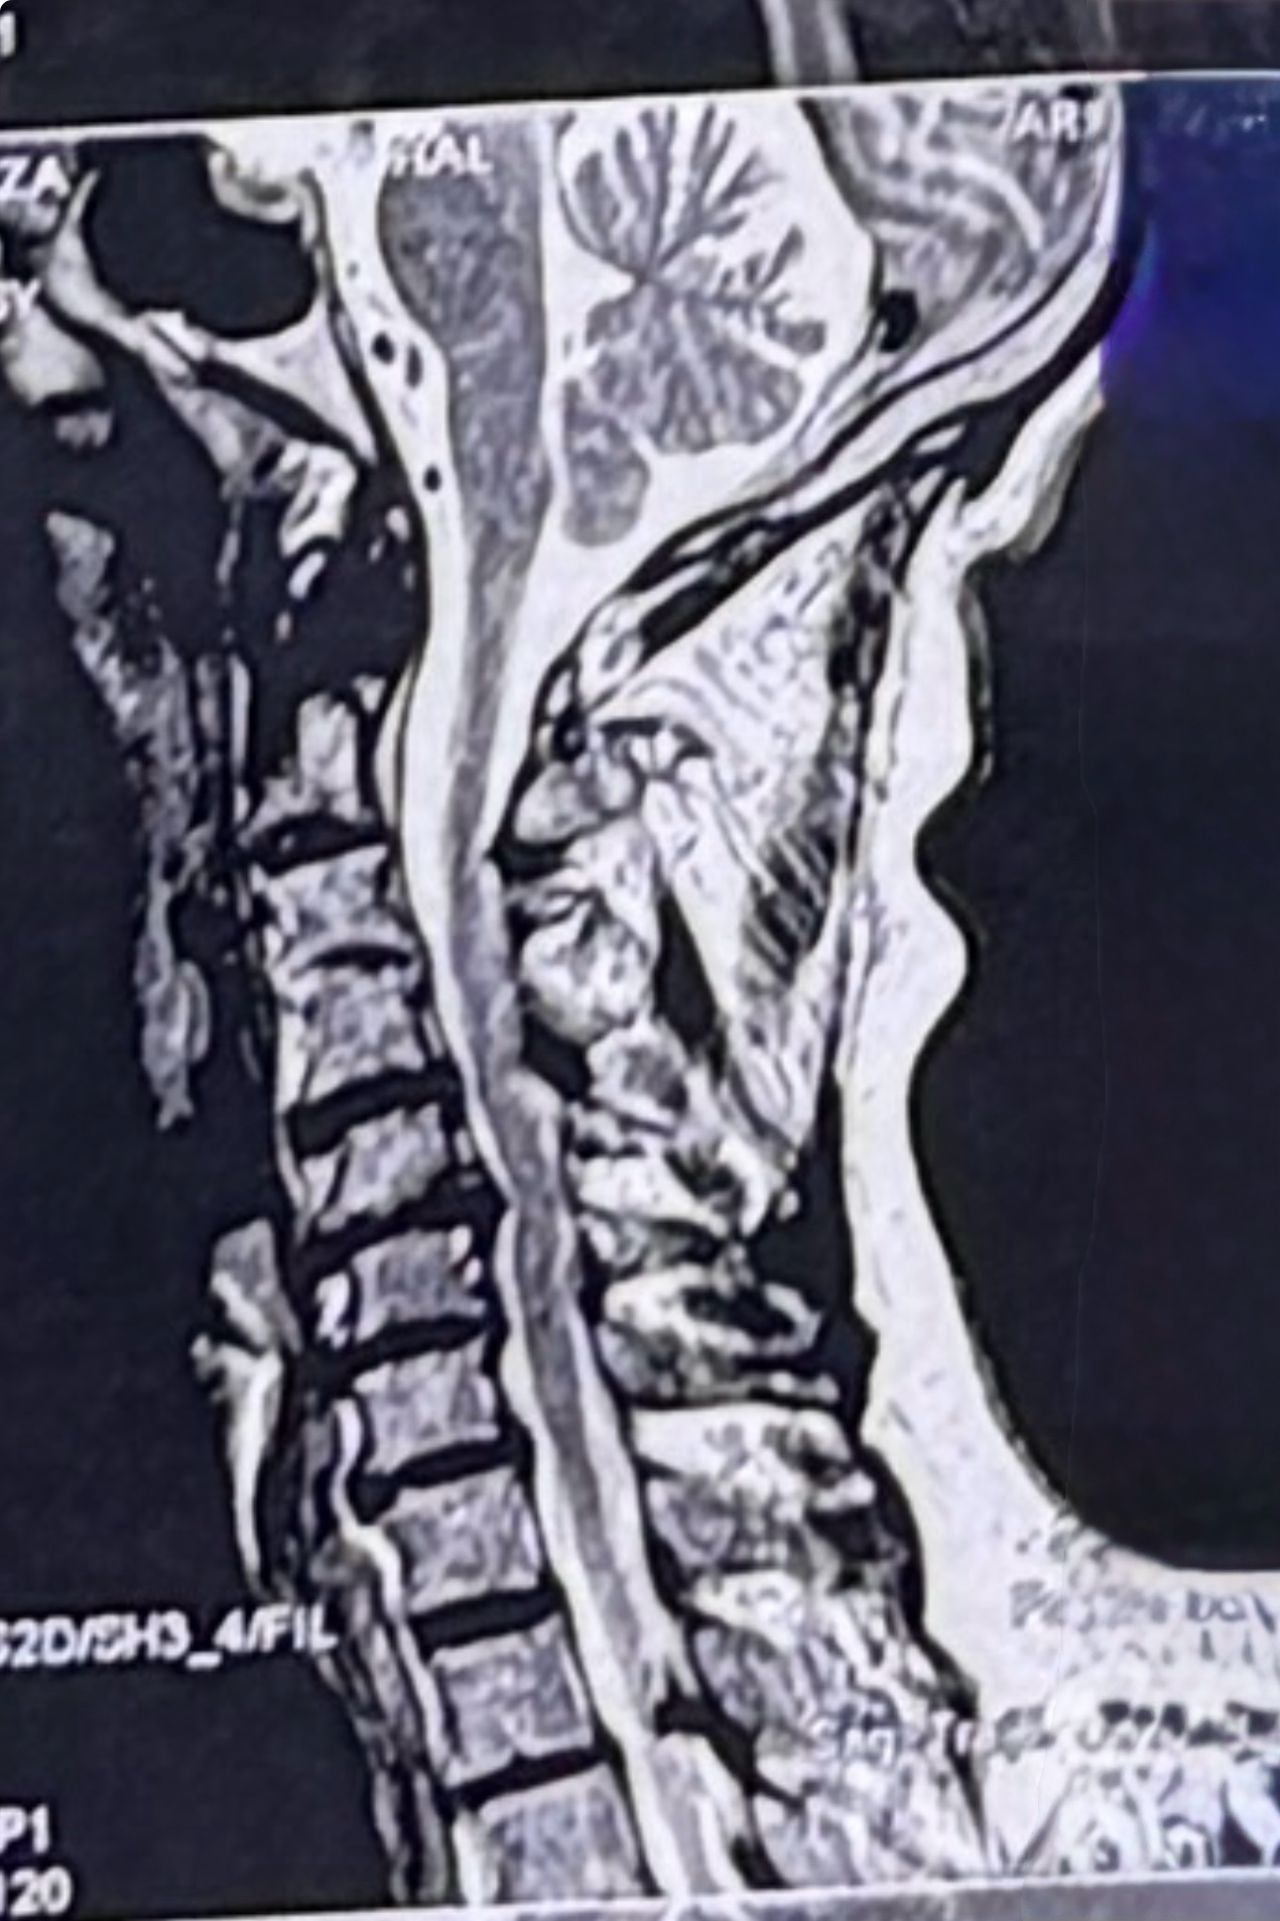

A 64-year-old male patient was referred to my clinic by a well-known neurosurgeon (Oct 2025) for evaluation and management of right-sided sciatic pain. The onset followed an incident in which his 18-year-old grandson accidentally pulled his leg. Relevant medical documents were reviewed and attached. He just has controled DM

On presentation, the patient denied any cervical pain. Nevertheless, as part of my routine examination protocol, a comprehensive cervical assessment was performed, including chiropractic, orthopedic, and neurological evaluations. Cervical range of motion was markedly restricted, and chiropractic motion and static palpations revealed hypertrophic pillar segments and multiple severe Facets restrictions .There were no upper motor neuron (UMN) signs at all noted during the examination.

Investigations and Management;

A cervical and thoracic MRI was requested, and lumbar treatment was initiated for his sciatic symptoms. The patient was also advised to follow up with his neurosurgeon regarding the cervical findings.in his mri a large hydronephrosis was noticed and For his large hydronephrosis he was asked to see a nephrologist ( he mentioned he had ESWL for kidney stone few years ago)

Upon further discussion with the patient after reviewing his cervical MRI with him , the patient mentioned that he had previously fallen from a three-story building, sustaining ankle fractures at that time.after seeing his cervical mri the possibility of C4,5, and possibly retrolisthesis of C5 was considered and CT scan from C/S and dynamic cervical x ray was requested

Discussion

Although the patient was asymptomatic from a cervical standpoint, MRI findings demonstrated cervical cord severe compression and possible mild edema and early myelomalacia. Based on these findings, I believe that cervical decompression surgery should be considered.

While some neurologists and chiropractors may defer intervention in the absence of overt clinical symptoms, in this case, early surgical decompression appears justified. Waiting for neurological deficits—such as gait imbalance, coordination difficulties, or gastrointestinal/genitourinary dysfunction—may result in irreversible spinal cord injury, as these deficits often persist even after surgical decompression.

Considering the patient’s age and progressive degenerative changes, including degenerative disc disease (DDD) and degenerative joint disease (DJD), delaying surgery could further increase the risks associated with operative morbidity and mortality. Keep in mind all kind of manipulation on his neck is absolutely contraindicated

Conclusion;

Early identification and management of clinically silent cervical cord compression with MRI evidence with or without myelomalacia may prevent irreversible neurological deterioration in future.on the other hand he has to take care of his kidney seriously

I welcome interprofessional opinions and discussion regarding the optimal management strategy for this patient’s cervical spine pathology, particularly concerning the timing and indications for surgical decompression in the absence of overt cervical symptoms.